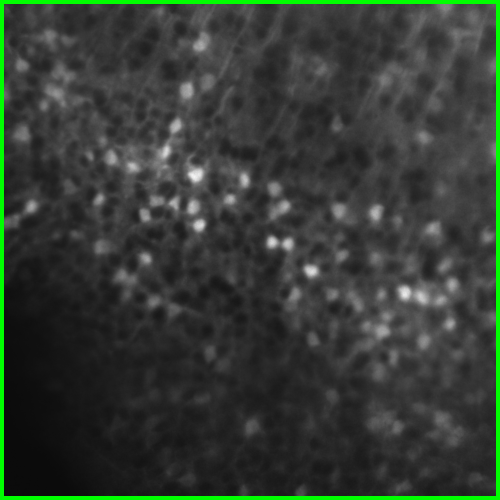

1.1 CLARITY

CLARITY avoids these problems by converting the brain into a translucent hydrogel-tissue hybrid. In the procedure, the brain is first perfused with hydrogel monomers and formaldehyde. When heated, the monomers and formaldehyde polymerize to form a molecular mesh which crosslinks amine groups of biological molecules. Since phospholipids lack amine groups, they do not crosslink with the mesh and can be eluted away with a strong detergent. The remaining hydrogel-brain hybrid is relatively translucent and permeable to fluorescent antibodies, making it amenable to labeling and interrogation by light-sheet microscopy. [2, 3] An axial slice through a CLARITY volume and magnified cutout are shown in Fig. 1.